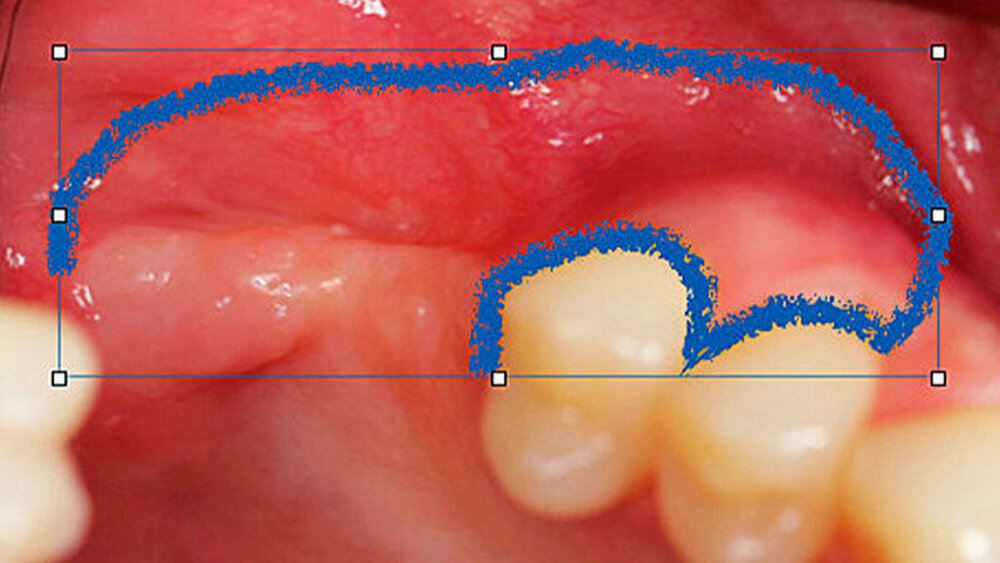

Die Schnittführung wurde nach dem Pillar-Sockel-Design (Blume) vorgenommen. Dabei liegt die Inzision weit im Vestibulum und verbindet zwei vertikale Entlastungsschnitte. Im Gegensatz zu der herkömmlichen krestalen Schnittführung bleibt das Periost über dem augmentierten Bereich damit völlig intakt. Nach der streng subperiostalen Präparation erfolgte die Kontrolle der Passung des CAD/CAM-Blocks. Ein ganz entscheidender Punkt ist, vor jeglichem Kontakt des Blockes mit Blut diesen in steriler Kochsalzlösung und am besten in der PRF-Flüssigkeit zu wässern, sodass sich keine Poren des Blocks mit Blutkoageln verschließen und innerhalb des Blocks ein nicht mit Blut gefüllter Hohlraum bildet. Vor der Befestigung des Blocks wurde die Kompakta des Empfängerbetts mit einer kleinen Kugelfräse mehrfach perforiert um sogenannte Bleeding Points zu setzen, die die Durchblutung des Knochenblocks gewährleisten. Mit zwei Osteosyntheseschrauben mit dem Durchmesser 1,5 mm und der Länge 9 mm wurde der allogene Knochenblock rotationssicher fixiert. Das Augmentat wurde mit einer dünnen Schweinepericard-Membran (Jason membrane, botiss biomaterials GmbH, Vertrieb Straumann) und der PRF-Membran abgedeckt. Der spannungsfreie Wundverschluss erfolgte mit der modifizierten vertikalen Matratzennaht nach Laurrell mit resorbierbarem Nahtmaterial (Vicryl 4.0). Postoperativ wurde ein Oberkiefer-DVT angefertigt. Die Nahtentfernung wurde im Rahmen der Nachsorgeuntersuchung sieben und 14 Tage postoperativ vorgenommen. Nach einer Heilzeit von sechs Monaten erfolgte die Implantation in Lokalanästhesie unter antibiotischer Abschirmung mit 2 g Amoxicillin oral eine Stunde präoperativ. Die Schnittführung erfolgte krestal, und nach subperiostaler Präparation wurde der Knochenblock dargestellt und die Osteosyntheseschrauben wurden entfernt. Danach wurden drei Implantate (Straumann) in den Knochenblock gesetzt und mit 0er-Verschlussschrauben abgedeckt. Die Wundrandadaptation erfolgte mit resorbierbarem Nahtmaterial, das bei der Verlaufskontrolle sieben Tage postoperativ vollständig entfernt wurde. Nach dreimonatiger gedeckter Einheilung wurden die Implantate im Rahmen einer Vestibulumplastik freigelegt. Dafür wurde eine erneute krestale Schnittführung regio 14 bis 17 vorgenommen und ein Splitflap präpariert. Der vestibuläre Wundrand wurde mit Einzelknopfnähten im Vestibulum fixiert. Im Bereich der Implantate wurde der Splitflap perforiert, um die Abdeckschrauben gegen Gingivaformer auszutauschen, und der Bereich des nun freiliegenden Bindegewebes wurde mit einer 3D-vernetzten Kollagenmatrix (mucoderm, botiss biomaterials GmbH, Vertrieb Straumann) abgedeckt. Diese wurde zunächst gewässert, um die Verarbeitung zu erleichtern, und an den Stellen der Gingivaformer gestanzt. Die Nahtentfernung erfolgte neun Tage postoperativ. (Abb. 1a bis 1f).

Ein 29-jähriger Patient stellte sich mit einer massiven Alveolarkammatrophie im rechten Unterkiefer in unserer Praxis vor. Diese lag in langen Jahren der Zahnlosigkeit begründet. Eine Beckenkammaugmentation kam für den Patienten nicht in Betracht. Dennoch wünschte er die Versorgung mit festsitzendem Zahnersatz. Nach ausführlicher Beratung entschied sich auch dieser Patient für eine Augmentation mit einem patientenindividualisierten allogenen CAD/CAM-gefertigten Knochenblock. Die DICOM-Daten des Unterkiefer-DVTs wurde an die Firma Zimmer gesendet, und es erfolgten wie im oben beschriebenen Fall eine virtuelle Planung und das virtuelle Design des allogenen Knochenblocks anhand der geplanten Implantatpositionen. Nach der üblichen Kontrolle und Freigabe des Chirurgen erfolgte die eigentliche Fertigung und Übersendung des Knochenblocks in die Praxis. Die Augmentation erfolgte auch in diesem Fall in Vollnarkose unter antibiotischer Abschirmung perioperativ mit Ampicillin. Die Schnittführung im Unterkiefer unterscheidet sich von der Sockelschnittführung im Oberkiefer aufgrund der Anatomie (N. mentalis). Auch bei diesem Patienten wurde eine tief im Vestibulum liegende bogenförmige Inzi‧sion durchgeführt, jedoch ohne die vertikalen Entlastungen. Nach streng subperiostaler Präparation erfolgte die Darstellung des N. mentalis. Die Vorbereitung des Spenderbetts sowie die Wässerung, Einpassung und Befestigung des allogenen Knochenblocks gestalteten sich wie im Fallbeispiel 1. Die Heilzeit des Knochenblocks dauerte ebenfalls sechs Monate. Zwei Implantate (Straumann) wurden nach krestaler Schnittführung in Lokalanästhesie eingebracht und heilten subgingival binnen drei Monaten ein. Aufgrund des massiven Volumenzuwachses war auch ebenfalls eine Vestibulumplastik im Zuge der Implantatfreilegung notwendig. Das Prozedere verlief ebenfalls wie im Fallbeispiel 1. Das freiliegende Gewebe wurde mit einer Kollagenmatrix abgedeckt. Dadurch konnte die Breite der befestigten Gingiva deutlich verbreitert werden.